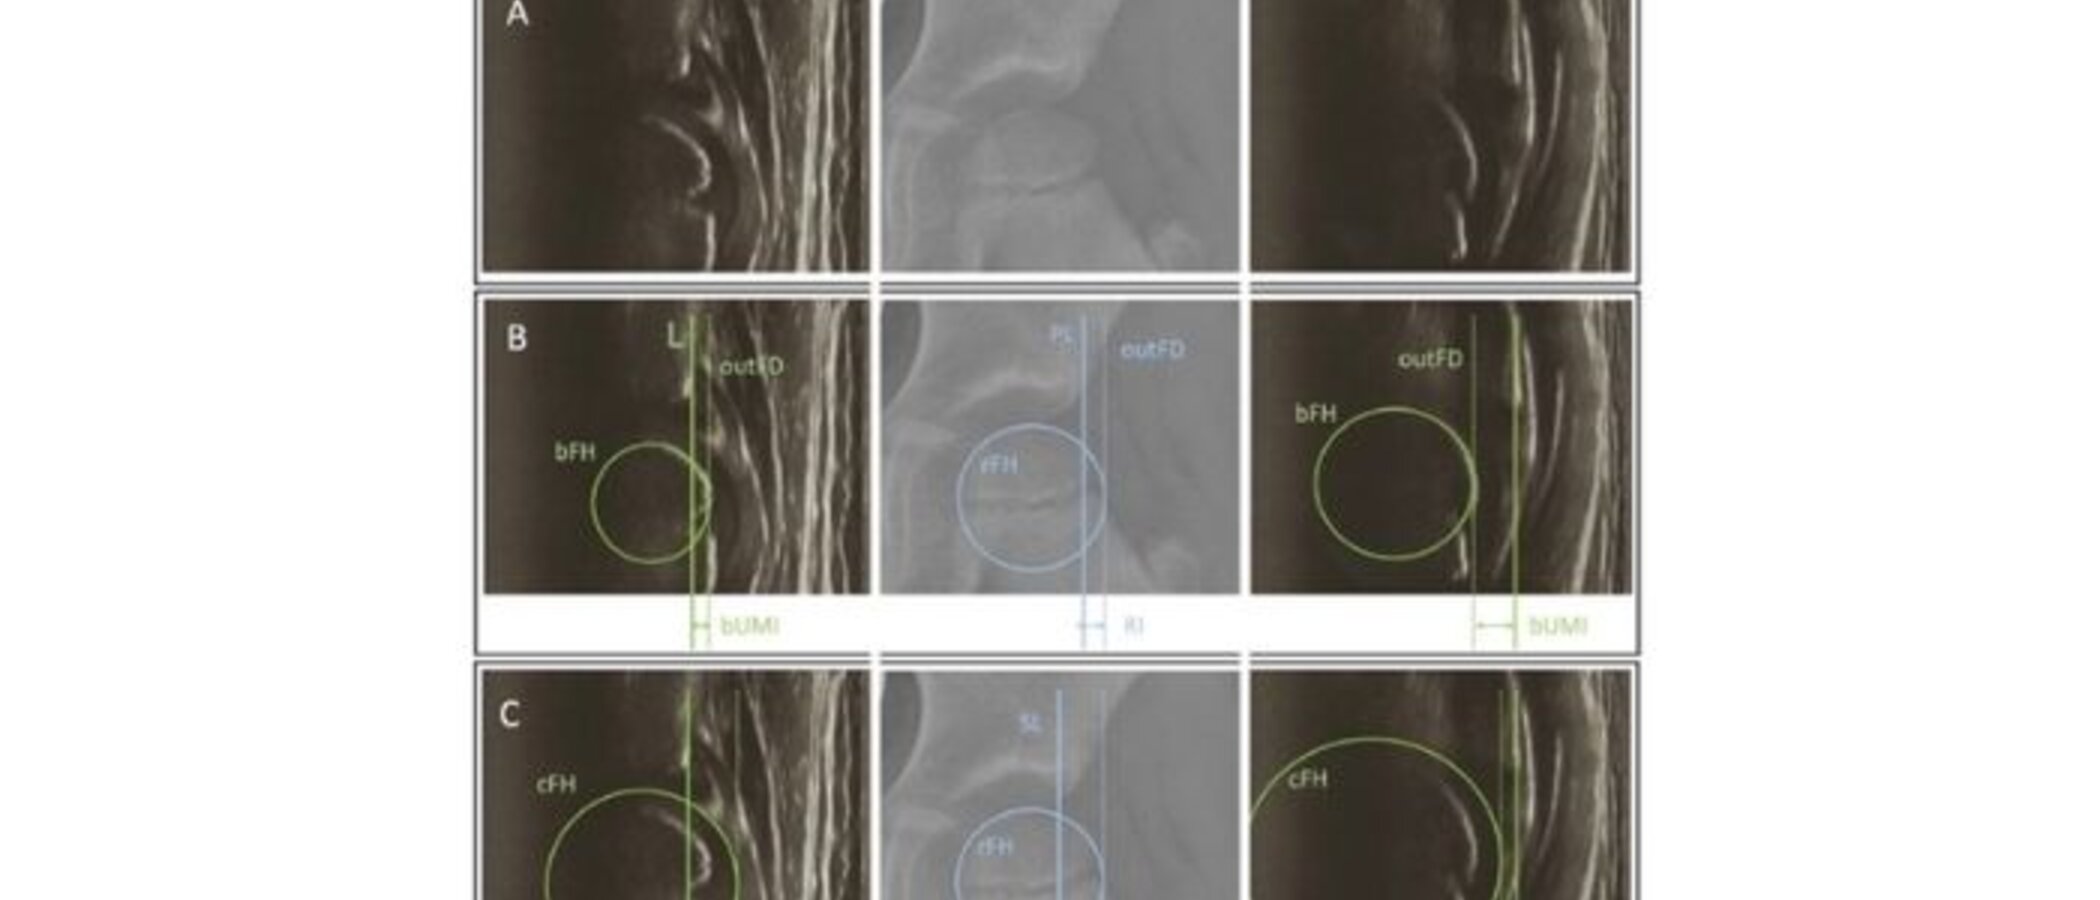

Kinder mit Zerebralparese (CP) oder einer angeborenen Hüftreifungsstörung (DDH) brauchen regelmäßige Hüftkontrollen, damit ein „Weglaufen“ des Hüftkopfs aus der Pfanne (Dezentrierung) früh erkannt und behandelt werden kann. Röntgen ist dafür üblich – bedeutet aber Strahlenbelastung. Die Studie prüft, ob Ultraschall (US) als strahlenfreie Alternative das Gleiche zuverlässig feststellen kann.

Aus beiden Verfahren wurden vergleichbare Messgrößen berechnet, die anzeigen, wie weit der Hüftkopf seitlich „heraussteht“.

• Aussagekraft: Ultraschall und Röntgen lieferten für bestimmte standarisierte radiologische Parameter sehr ähnliche Messwerte. Es gab keinen bedeutsamen Unterschied zwischen den zentralen Kennzahlen beider Verfahren. → US ist verlässlich.

• Hohe Zuverlässigkeit: Wenn verschiedene Untersucher*innen oder die gleiche Person erneut messen, kommen nahezu identische Ergebnisse heraus. → US ist reproduzierbar.